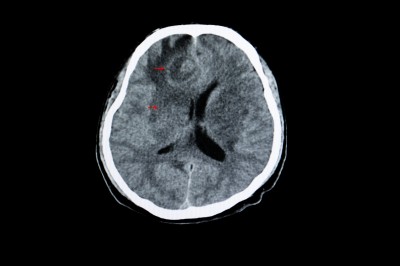

对于脑膜转移伴随的呕吐症状,主要考虑两个原因,一个是颅高压,一个是肿瘤直接刺激呕吐中枢。无论是哪个原因,症结都是肿瘤,如果抗肿瘤有效,症状就有机会缓解。

对于颅高压的患者,分流手术可以显著改善恶心呕吐的问题,虽然手术后胃口仍然不好,但至少进食后不容易呕吐。但如果没有颅高压,即便有脑水肿、脑积水表现,分流的效果就非常有限了。

需要腰穿确认颅内压力,只在颅高压时使用甘露醇,并且在应用甘露醇时补充水分和电解质,定期抽血评估电解质等指标。对于顽固性颅高压,靶向药无法缓解颅内压增高的情况下,可以选择分流手术。